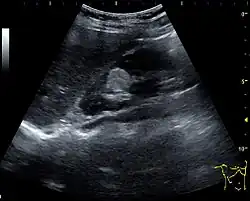

A solid renal mass appears in the US exam with internal echoes, without the well-defined, smooth walls seen in cysts, often with Doppler signal, and is frequently malignant or has a high malignant potential. The most common malignant renal parenchymal tumor is renal cell carcinoma (RCC), which accounts for 86% of the malignancies in the kidney. RCCs are typically isoechoic and peripherally located in the parenchyma, but can be both hypo- and hyper-echoic and are found centrally in medulla or sinus. The lesions can be multifocal and have cystic elements due to necrosis, calcifications and be multifocal (Figure 8 and Figure 9). RCC is associated with von Hippel–Lindau disease, and with tuberous sclerosis, and US has been recommended as a tool for assessment and follow-up of renal masses in these patients.[1]

Figure 10. Solid tumor in the renal sinus seen as a hypoechoic mass, later found to be lymphoma. The '1' and '2' on the US image are reference points used for CT fusion (not shown).[1] -